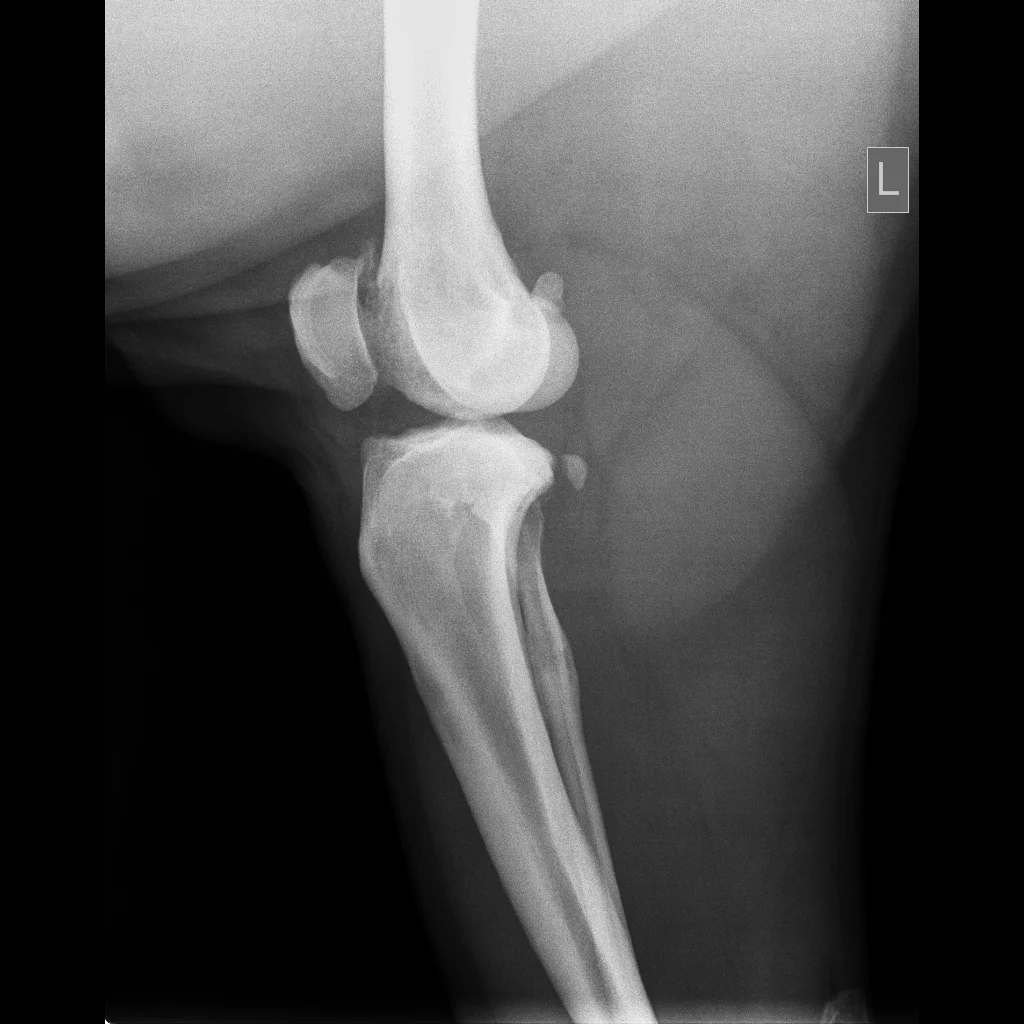

The two photos below show two stifle joints (knees) of a bear at the Chengdu Bear Rescue Centre. You can see the difference between the two, the L labelled joint has spiky pieces and haziness around the edge of the bone in the joint, these changes are secondary to DJD.